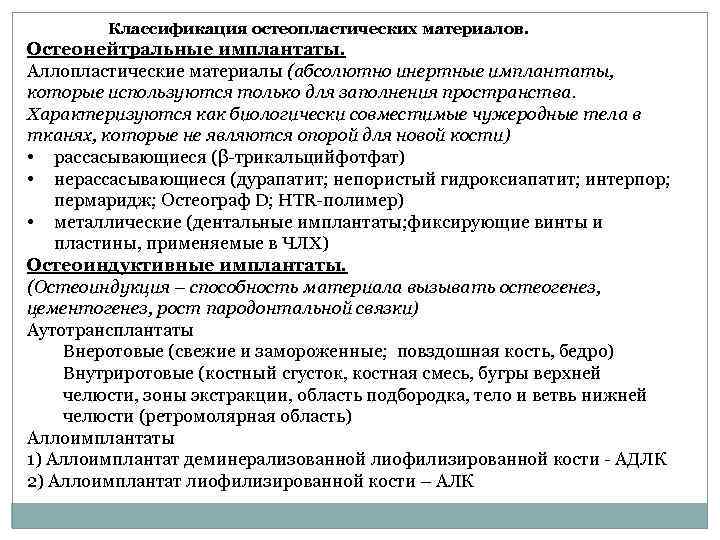

Классификация остеопластических материалов. Остеонейтральные имплантаты. Аллопластические материалы (абсолютно инертные имплантаты, которые используются только для заполнения пространства. Характеризуются как биологически совместимые чужеродные тела в тканях, которые не являются опорой для новой кости) • рассасывающиеся (β трикальцийфотфат) • нерассасывающиеся (дурапатит; непористый гидроксиапатит; интерпор; пермаридж; Остеограф D; HTR полимер) • металлические (дентальные имплантаты; фиксирующие винты и пластины, применяемые в ЧЛХ) Остеоиндуктивные имплантаты. (Остеоиндукция – способность материала вызывать остеогенез, цементогенез, рост пародонтальной связки) Аутотрансплантаты Внеротовые (свежие и замороженные; повздошная кость, бедро) Внутриротовые (костный сгусток, костная смесь, бугры верхней челюсти, зоны экстракции, область подбородка, тело и ветвь нижней челюсти (ретромолярная область) Аллоимплантаты 1) Аллоимплантат деминерализованной лиофилизированной кости АДЛК 2) Аллоимплантат лиофилизированной кости – АЛК